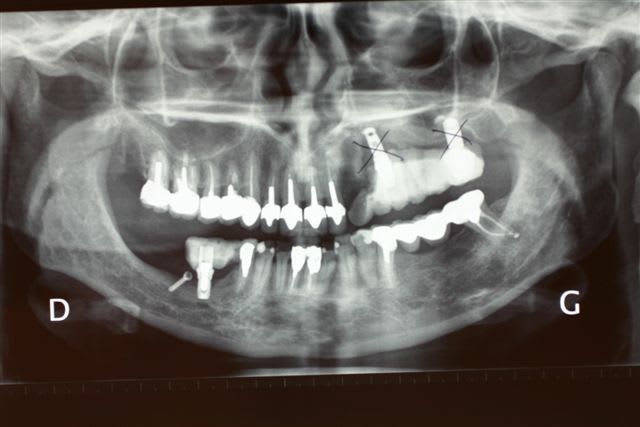

Perte d un greffon iliaque

Retraité en basale voici 6 ans avec succès